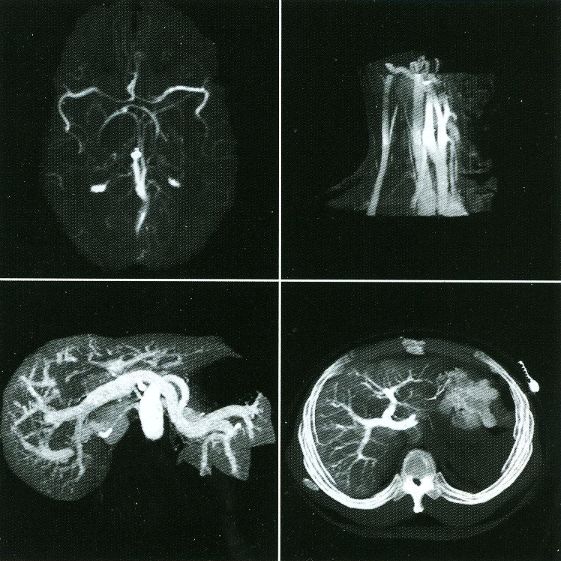

Here are typical examples of VoxelQ displays. These are mostly only windows, not the full screen which is more along the lines of the last block of AcQSim photos.

VoxelQ Multiplanar Reformatting (Axial, Saggital, Coronal, Curved)

VoxelQ Shaded Surface

VoxelQ Volume Rendering

VoxelQ Segmentation

VoxelQ Virtual Endoscopy

While the VPP and Voxelscopes I and II rendered "back-to-front" to implement hidden surface removal, the redesigned VoxelQ hardware was optimized for ray tracing with volume rendering capabilities. VQ projected a ray from each pixel on the display back through the object and was able to perform computations along the way. An innovative sub-voxel search algorithm rendered much more realistic surfaces using relatively simple surface shading algorithms. Even Anthony was impressed with the image quality when this technique was first simulated in software with the intent of incorporating it into the microcode - and he was most familiar what else was being done in software, which could render the best images since there were fewer time constraints. In addition to hidden surface removal and gradient shading, this approach supports various forms of transparency with perspective enabling the simulation of X-ray views ("reprojection") as well as rendering translucent organs. Many of the changes were implemented in microcode with relatively small changes to the actual hardware. But the key innovation that differentiated VoxelQ from the machines before it was the "Object Resampling Memory" (ORM) which generated tri-linearly interpolated voxel data based on full 3-D coordinates. Essentially, the eight adjacent voxels closest to the specified coordinate in the original dataset were accessed simultaneously and an interpolated result was computed auto-magically. For successive coordinates that were close together (as they would be for ray tracing), the effective throughput could approach 10 million tri-linearly interpolated voxels per second. The ORM was the only totally new custom board and replaced the MicroVAX memory.

Shading of the rendered objects is essential to the perception of 3-D depth in a static display of a single image (no stereo). Motion parallax also contributes to this but only if the update rate is high enough. The VPP only had "depth shading", whereby each pixel's value was modified by distance from the viewer. Subsequent machines used "gradient shading" which also calculated the local rate-of-change of the surface to modulate the pixel intensity. While this was not photo-realistic, the overall effect was quite satisfactory at a much lower computational cost. And with the tri-linearly interpolated voxels, the result was actually quite impressive.